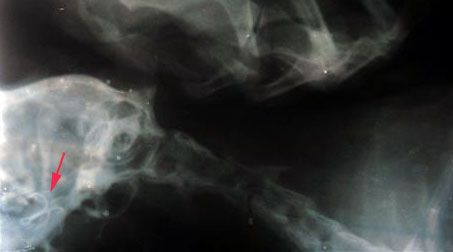

Comme tous les chats, Kéro (le chat des parents) aime manger. Un peu de tout. Aujourd'hui il a expérimenté... les hameçons. Comme vous pouvez le voir sur la radiographie, il n'a pas vraiment digéré.

Le pauvre s'est retrouvé chez le vétérinaire pour une opération assez sérieuse. Mais je vous rassure ses jours ne sont plus en danger.